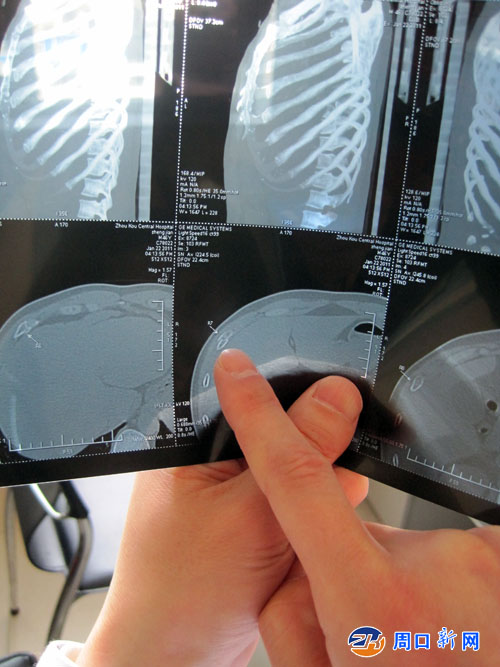

醫院CT診斷書 (王濤 攝)

醫生指出骨折位置

事情回顧:1月21日晚上8點30分,淮陽縣城關鎮第三中學九五班學生任志遠、劉志鵬、石祖明、任棒、靳凱5名同學放學回家,沿校外西側柏油路向北走,大路邊突然冒出六名滿身酒氣的社會青年,有位青年大聲問道,“哪的?”任志遠他們回答說我們是三中的學生,話音未落,這六名社會青年群涌而上,對幾名學生拳打腳踢,大打出手,任志遠等5名學生被打倒在地滿臉是血,任志遠爬起后跑到學校找老師,九五班班主任鄭健正好出門回家,聞訊后立即和學生跑向事發地點,邊跑邊喊“我是三中老師,不要打學生”,然而這群暴徒囂張至極,并對鄭健老師痛下毒手,經醫院CT診斷發現右側第5、6、7、8根肋骨全部骨折,肺部受傷。